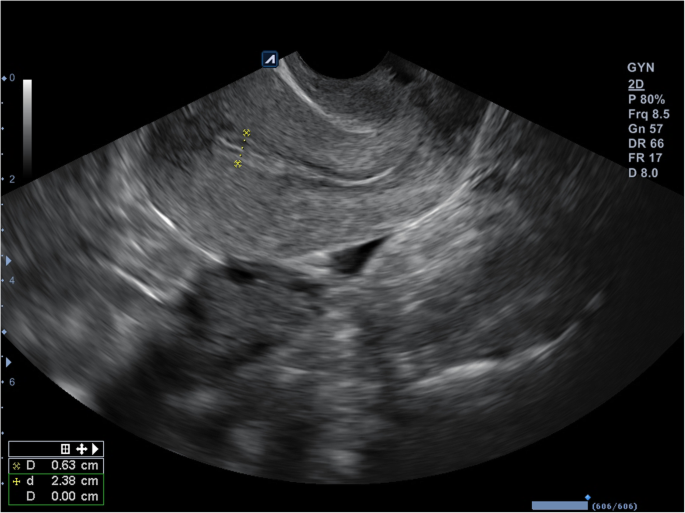

On the day of hysteroscopy, the patient began to take estradiol valerate 2.0 mg, at two tablets daily by mouth. After 3 days, a gel of estradiol hemihydrate 1.0 mg was added, one sachet daily transdermally. Thirteen days after hysteroscopy, ultrasound monitoring of the endometrium was performed, and progesterone 200 mg was prescribed, one tablet three times daily by mouth. On the sixth day of the progesterone application, the thickness of the patient’s endometrium was 0.63 cm after ultrasound monitoring (Figs. 4 and 5). At the patient’s insistence, two embryos were transferred that day.